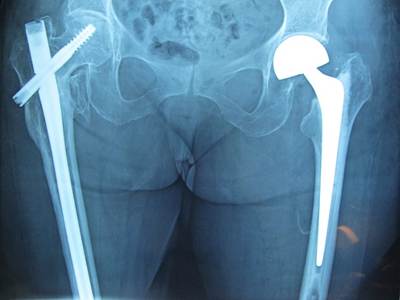

Σχετικά με τα απαρεκτόπιστα κατάγματα του αυχένα του μηριαίου οστού αντιμετωπίζονται κατά κανόνα με κοχλίωση, ενώ τα παρεκτοπισμένα με αρθροπλαστική συνήθως ημιαρθροπλαστική ή ολική αρθροπλαστική ισχίου σε νεότερους και δραστήριους ασθενείς. Τα διατροχαντήρια και υποτροχαντήρια κατάγματα αντιμετωπίζονται με ανοικτή ανάταξη και εσωτερική οστεοσύνθεση, κυρίως με ενδομυελικό ήλο ισχίου ή, σε σταθερές περιπτώσεις, με ολισθαίνοντα κοχλία. Η μη χειρουργική αντιμετώπιση είναι εξαιρετικά περιορισμένη και αφορά μόνο πολύ σταθερά κατάγματα ή ασθενείς με ιδιαίτερα επιβαρυμένο ιατρικό ιστορικό και ελάχιστη προϋπάρχουσα κινητικότητα.